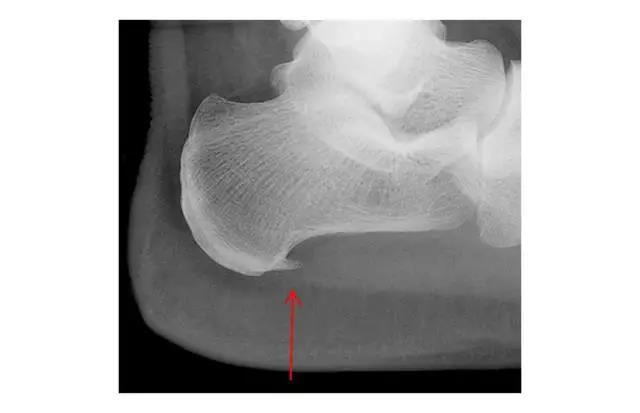

被冤枉的足跟骨刺

如下图(红色箭头所指),跟骨骨刺看着就让人觉着疼,所以“骨刺”在大家心目中被妖魔化成了足跟痛的罪魁祸首。但其实足跟骨刺并不是导致脚底跟疼痛的原因,研究表明,有足跟骨刺的人群中,63%的人是没有任何的疼痛症状。

足跟骨刺是跟骨骨质的增生,跖筋膜活动过多,过度收缩变得紧张,造成跖筋膜有细微的撕裂和发炎变得不舒服,造成了跖底筋膜炎这时人体的自我保护机制形成骨刺,想要保护过度收缩的而受伤的跖筋膜。